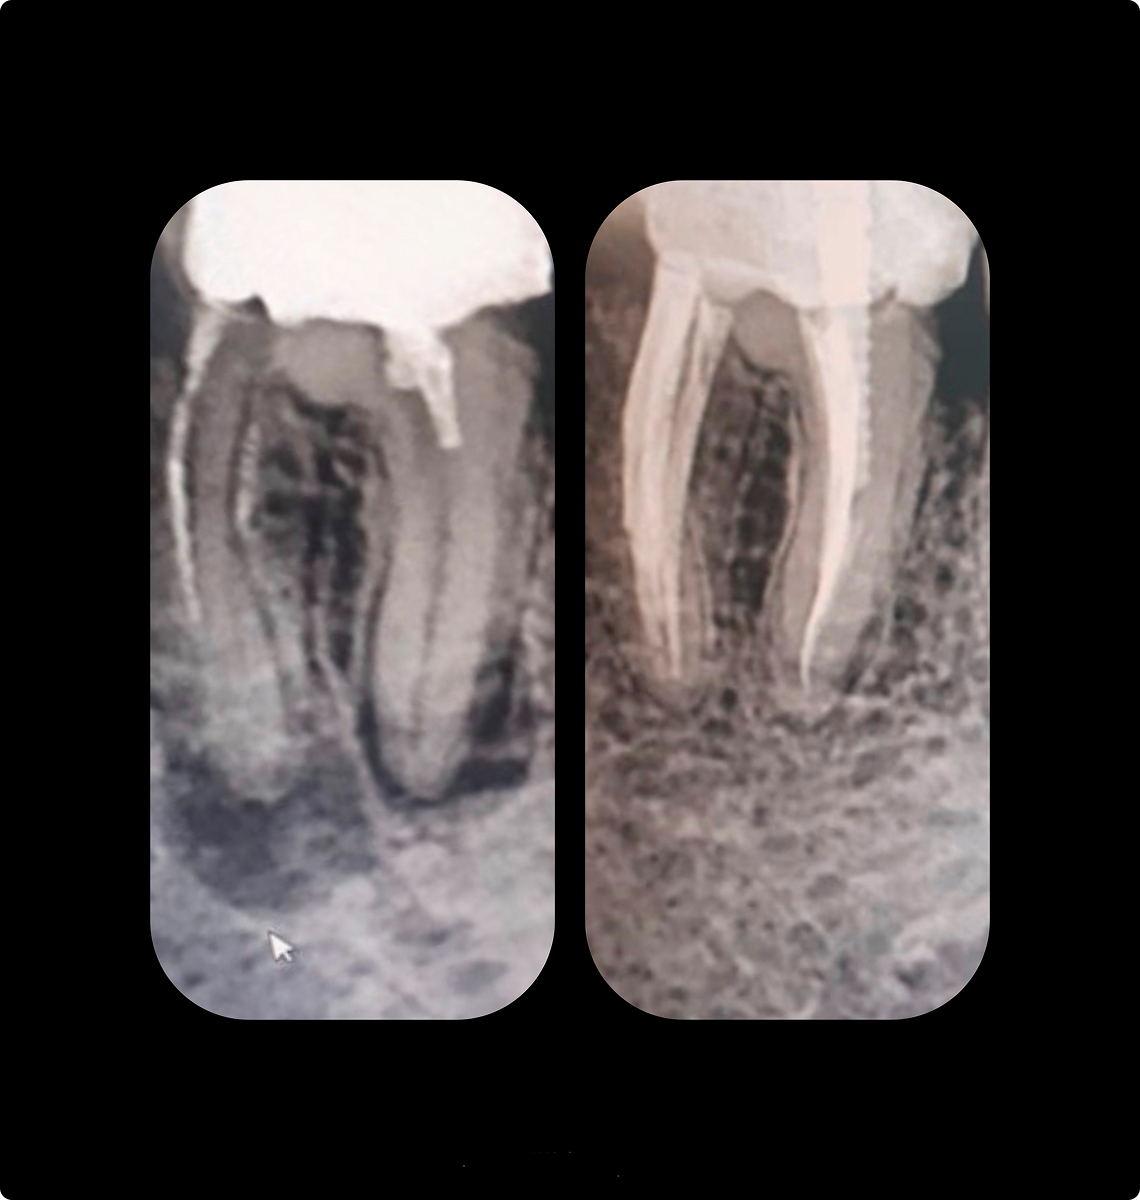

Современное эндодонтическое лечение практически невозможно без использования средств оптического увеличения: поиск узких корневых каналов, перелечивание каналов, диагностика трещин и перфораций, извлечение штифтов, отломков инструментов. С появлением оптики жизнь стоматолога стала ярче, насыщеннее и интереснее, ведь открылся новый взгляд, без всяких преград.

Эндодонтист – это врач узкой специализации, объектом внимания которого становятся корневые каналы зубов.

Эндодонтист работает со скрытыми, практически невидимыми структурами зуба. Для этого и используется увеличение – бинокулярные лупы со степенью увеличения от 5 и более раз, делающее скрытое явным.

Работа с увеличением полностью изменила лечение зубов, ведь увеличение позволяет разглядеть малейшие и незначительные нюансы строения стенок каналов, которые могут влиять на здоровье зубов. Раньше врач мог пропустить канал или его ответвление, не заметить трещины в стенках зуба и каналов или не увидеть перфорацию корня. Все это приводило к неправильно выбранной тактике лечения корневых каналов и было огромное количество осложнений, к сожалению, приводящее к потере зуба. Теперь под направленным светом и с увеличением эндодонтист не пропустит ничего.